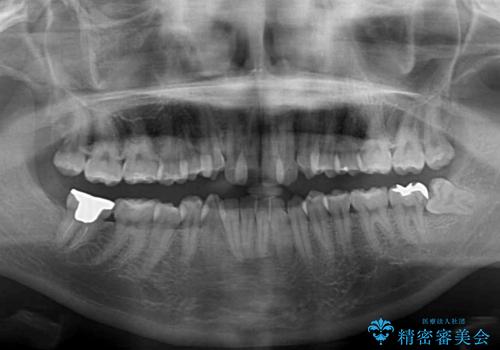

叢生の程度は中等度であったため、IPR(歯と歯の間を削る)と歯列の側方拡大をメインに、インビザラインを用いて歯列を改善することとしました。

また、下顎骨の右側変位による右側臼歯の咬合を改善させるよう試みることとしました。

右側の咬合改善を目標に様々な手法を用いましたが、骨格的なズレによる不正咬合はインビザラインでは改善することができませんでした。